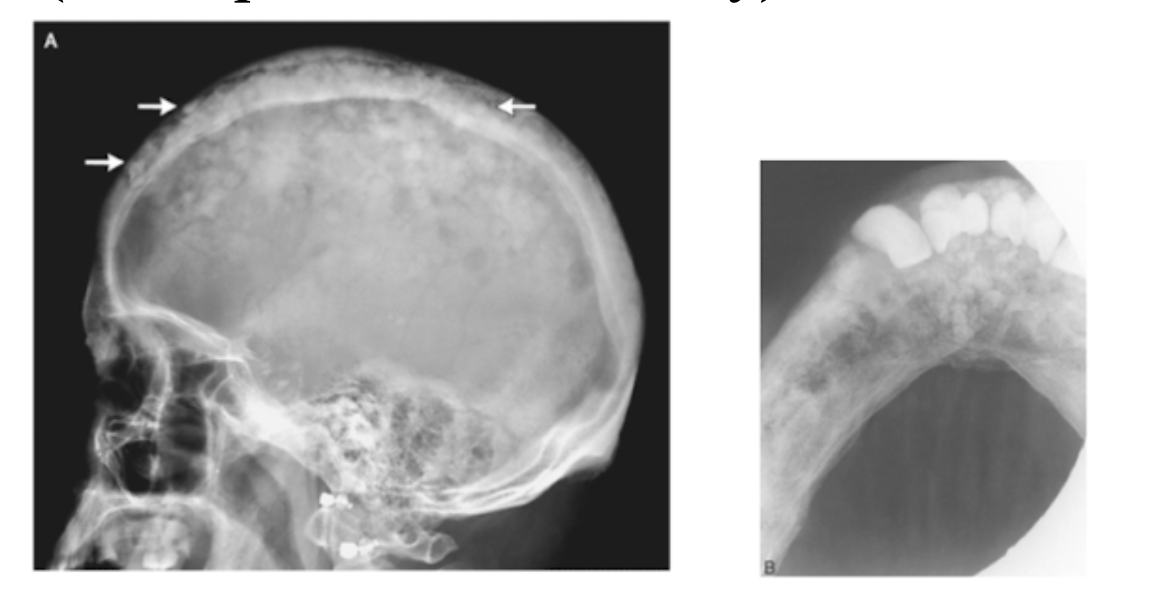

Paget’s Disease

A

Progressive Metabolic Disturbance of many bones (Spine, femur, skull, jaws)

* Causes symmetric enlargement

Cotton Wool Appearance

Adults > 50

* Increased Bone Breakdown=Elevated alkaline phosphate

* Denture & hats become too tight

Associated with:** hypercementosis**

Tx: Bisphosphonates & Calcitonin